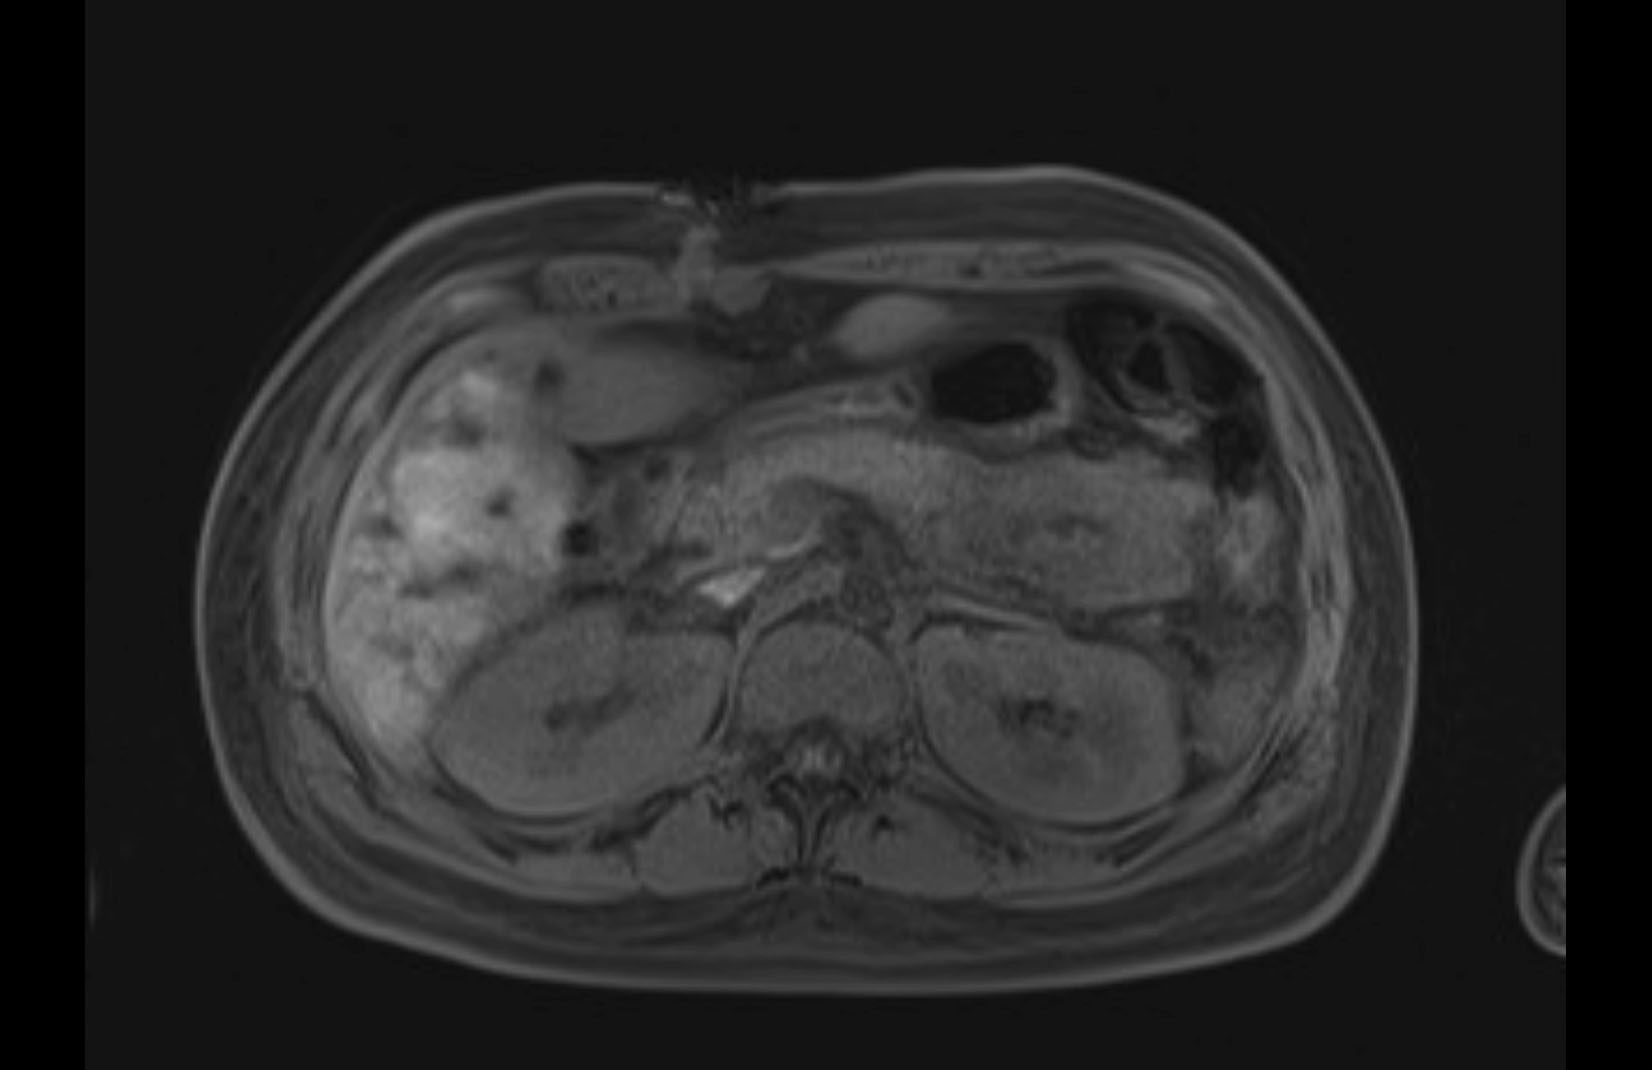

Imaging Analysis

Look through the patient's CT scan to identify any areas of concern for the necessary procedure.

MRI T1

MRI T2

Based on initial findings, which issue(s) would you be most concerned about?